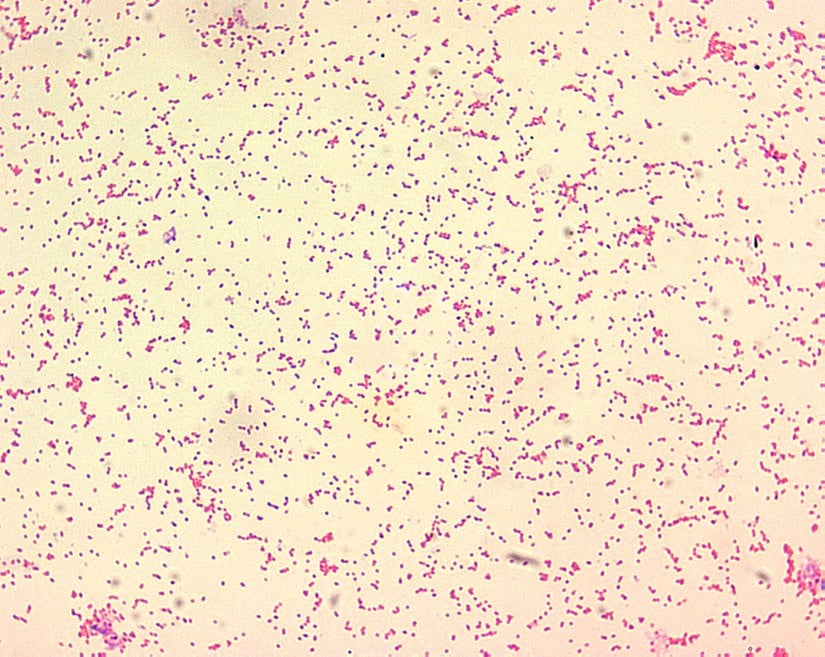

Brucella, Brucellaceae familyasında bulunmaktadır. Bu türler, Gram negatif, küçük kokoid çomak şeklinde, hareketsiz, sporsuz, aerofilik bakterilerdir. Bruselloz ise, Brucella cinsine ait bakteriyel türlerin yakından ilişkili olduğu yaygın bir zoonozdur. Bu hastalık, esas olarak kontamine süt ürünlerinin tüketilmesiyle insanlara bulaşmaktadır.

Salmonella cinsi bakteriler Enterobacteriaceae familyasında yer alan, gram negatif, sporsu, kapsülsüz, aerob ya da fakültatif anaerop, 20˚C- 40˚C arasında üreyebilen ve sahip olduğu peritriş dizilimli kirpikleri sayesinde hareketli mikroorganizmalardır. Salmonella enfeksiyonu genellikle ishal, ateş ve mide krampları şeklinde klinik tablolar oluşturmakla beraber idrarda, kanda, kemiklerde, eklemlerde veya sinir sisteminde (omurilik sıvısı ve beyinde) enfeksiyona neden olmakta ve ciddi hastalıklara sebebiyet vermektedir. Mikroorganizma insana kontamine et, süt ve suları tüketerek geçmektedir.

Enterobacteriaceae familyasında yer alan, gram negatif bir bakteridir. Escherichia coli (E. coli) bakterileri normalde insanların ve hayvanların bağırsaklarında flora üyesi olarak bulunmaktadır. E. coli' lerin büyük bir kısmı zararsızdır, bununla birlikte bazı E. coli türleri patojeniktir. Kişilerde diyare ve gastroentestinal hastalık dışı tablolarda kendini göstermektedir. Patojenik E.coli türleri çiğ süt, kirli su veya yiyecek yoluyla veya hayvanlarla temas yoluyla bulaşabilmektedir.